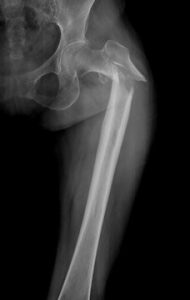

En el último vídeo del canal de ArtroEsport en YouTube, el Doctor Antoni Fraguas te explica una nueva técnica de femoroplastia para reforzar la osteoporosis femoral y evitar su fractura.

En el último episodio de Artro Esport Podcast, el Dr. Fraguas explica las innovaciones que previenen la fractura de fémur. Lo hace en este capítulo en formato entrevista. Asimismo, el

Existe una revolucionaria innovación que previene las fracturas de fémur en ancianos. Los que ya somos mayores hemos escuchado de nuestros abuelos que romperse el fémur a principios del siglo

Los que ya somos mayores hemos escuchado de nuestros abuelos que romperse el fémur a principios del siglo pasado era casi la condena de una muerte escalofriante. Imaginaos: en la